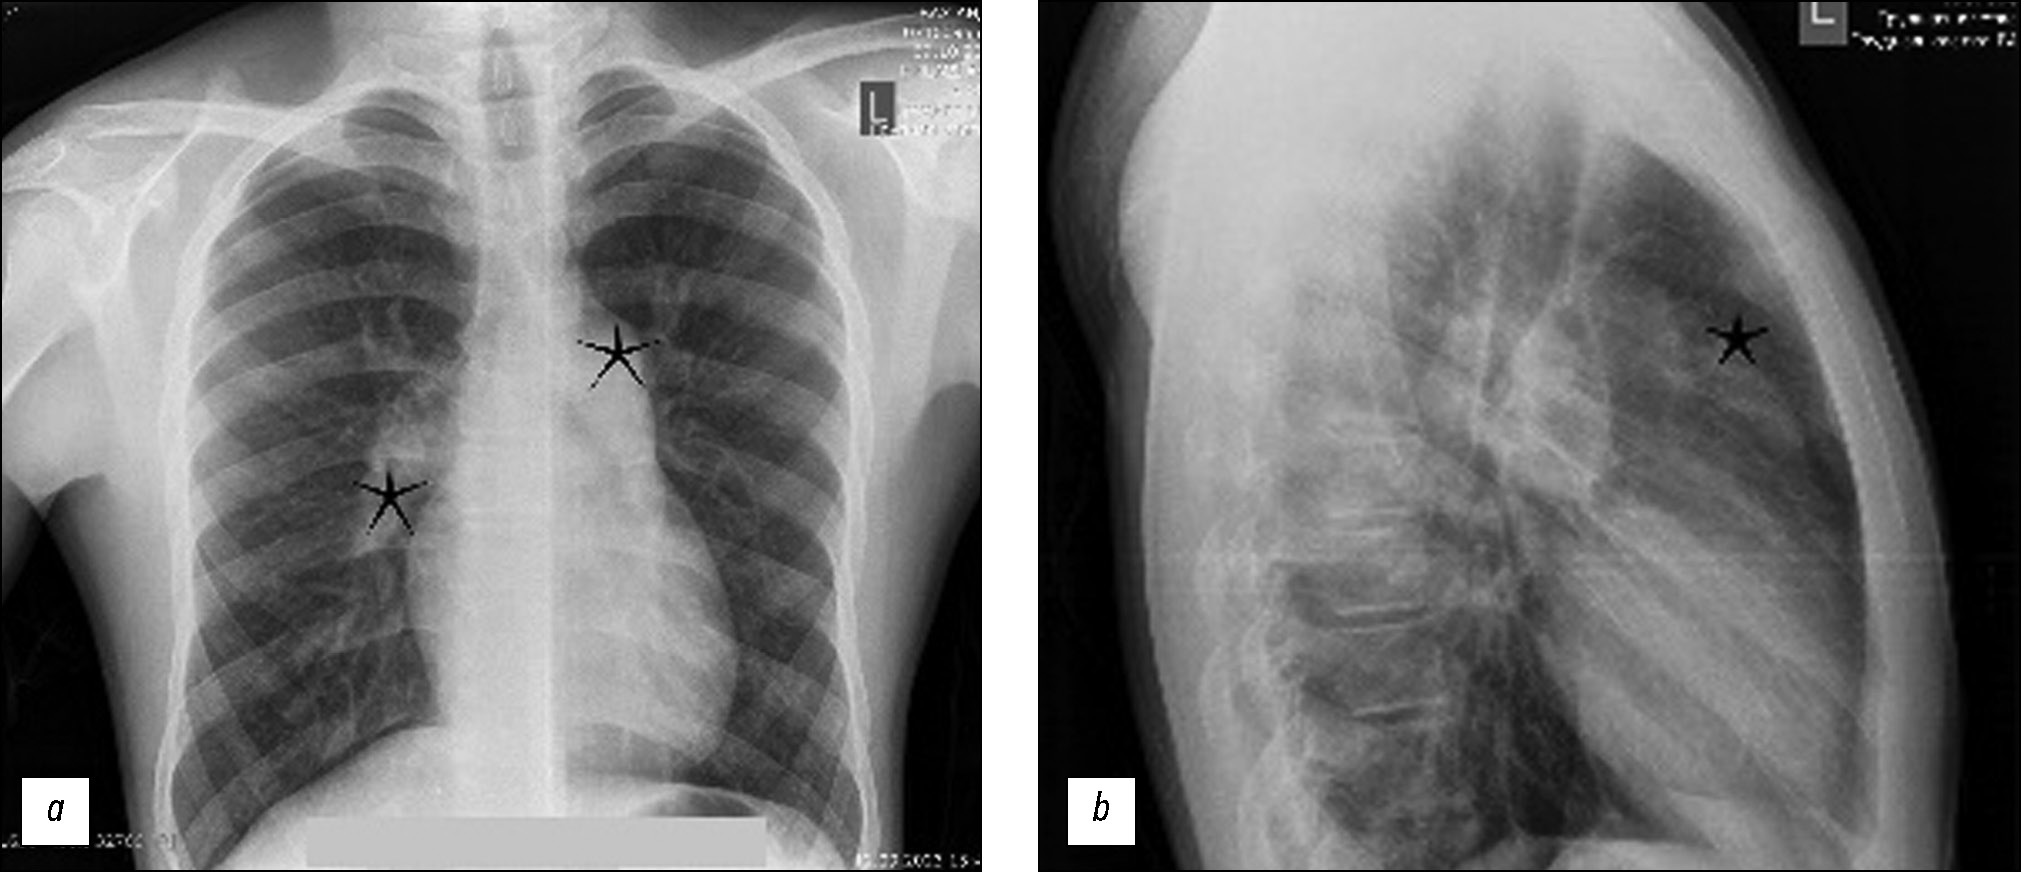

通过计算机断层扫描血管造影发现年轻肺动脉高压患者的肺动脉假性动脉瘤

假性动脉瘤和肺动脉瘤是一种罕见的疾病,但与之相关的并发症强调了识别它们的重要性。本文介绍了一名15岁患者的临床病例,该患者因咯血而入院。经诊断,发现左肺动脉瘤。随后的计算机断层扫描血管造影和肺动脉介入治疗结果证实存在肺动脉瘤,这表明咯血是由于动脉瘤破裂造成的。肺动脉介入证实了确诊。肺动脉瘤的早期发现和治疗至关重要,尤其是对年轻患者,因为及时干预可以预防严重并发症,改善疾病预后。提高对这些血管疾病的认识,并通过相应的诊断措施和干预措施对其进行及时处理,可以帮助医疗服务者有效降低与肺动脉瘤相关的潜在风险,从而提高预后准确性和医疗服务质量。